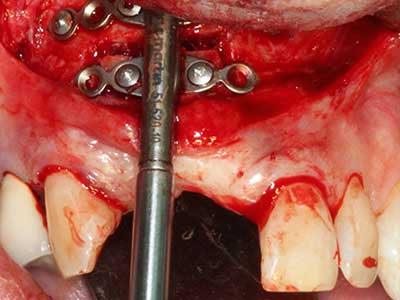

When surgical procedures are performed on bone in the immediate vicinity of sensitive structures such as blood vessels or nerves, rotary instruments pose a significant risk of iatrogenic injury. Piezoelectric devices can be helpful for preparation of bone covers and removal of hard tissue close to nerves, particularly for exposure of nerves after iatrogenic injury but also during nerve lateralization for resective and reconstructive procedures or implant placement (Fig. 17-20). Light contact between the piezotip and the nerve does not generally result in damage but proceeding incautiously with saw-like motions or attachments where a residual bone substrate remains may cause temporary or even permanent nerve damage. However, the risk of damage is considered to be substantially lower than when using saws or milling instruments (Pereira, Gealh et al. 2014).

Indication: Preparation near nerves

As noted above, indications for piezo surgery can also be found in the field of conservative dental surgery. Special working tips simplify the exposure of root tips and make it easier to protect nerves and sinus mucous membranes, particularly in the lower premolar and upper posterior tooth regions. Angled diamond tips are used to precisely prepare the resection cavity for the retrograde root filler material for unsealed apical obturation. The ultrasonic technology means the tips can be very slender, which improves the view and the size of the access cavity. As a result, the application of ultrasonic surgery for this indication is one of the standard procedures for apical resection (Del Fabbro, Tsesis et al. 2010, Scarano, Artese et al. 2012).